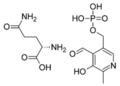

- 220px-Magnesium pyridoxal 5-phosphate glutamate.png سلام المجذوب

05:23، 10 سبتمبر 2012

220 × 158؛ 6 كيلوبايت